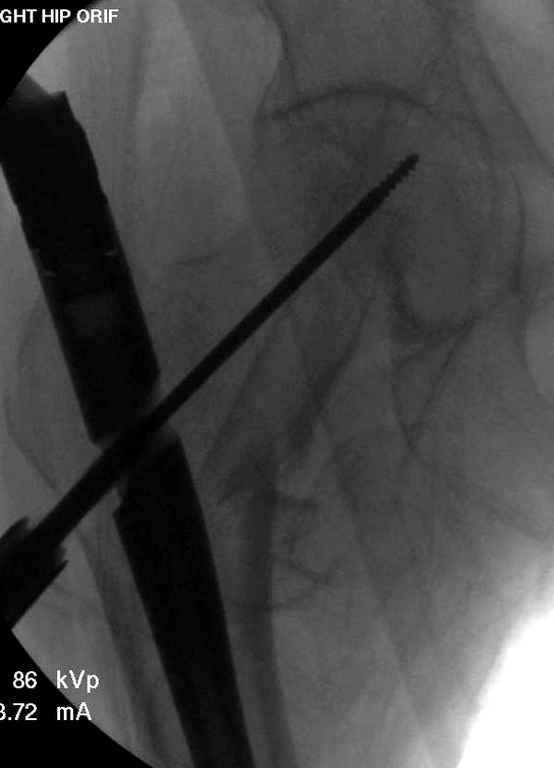

В приложении похожий пример, к счастью, пациентка появилась не после, а "за полчаса" до протрузии. Пересинтезировали с исправлением ошибок.

Вашему вниманию представляется похожий случай, пациентке 70, осложнился в течение одного месяца после операции. Ревизия с заменой сустава, кабельная фиксация на трохантер. При установке в дистальном диафизе обнаружен тонкий кортикальный слой и сделана профилактика от возможного перелома аллографтом.